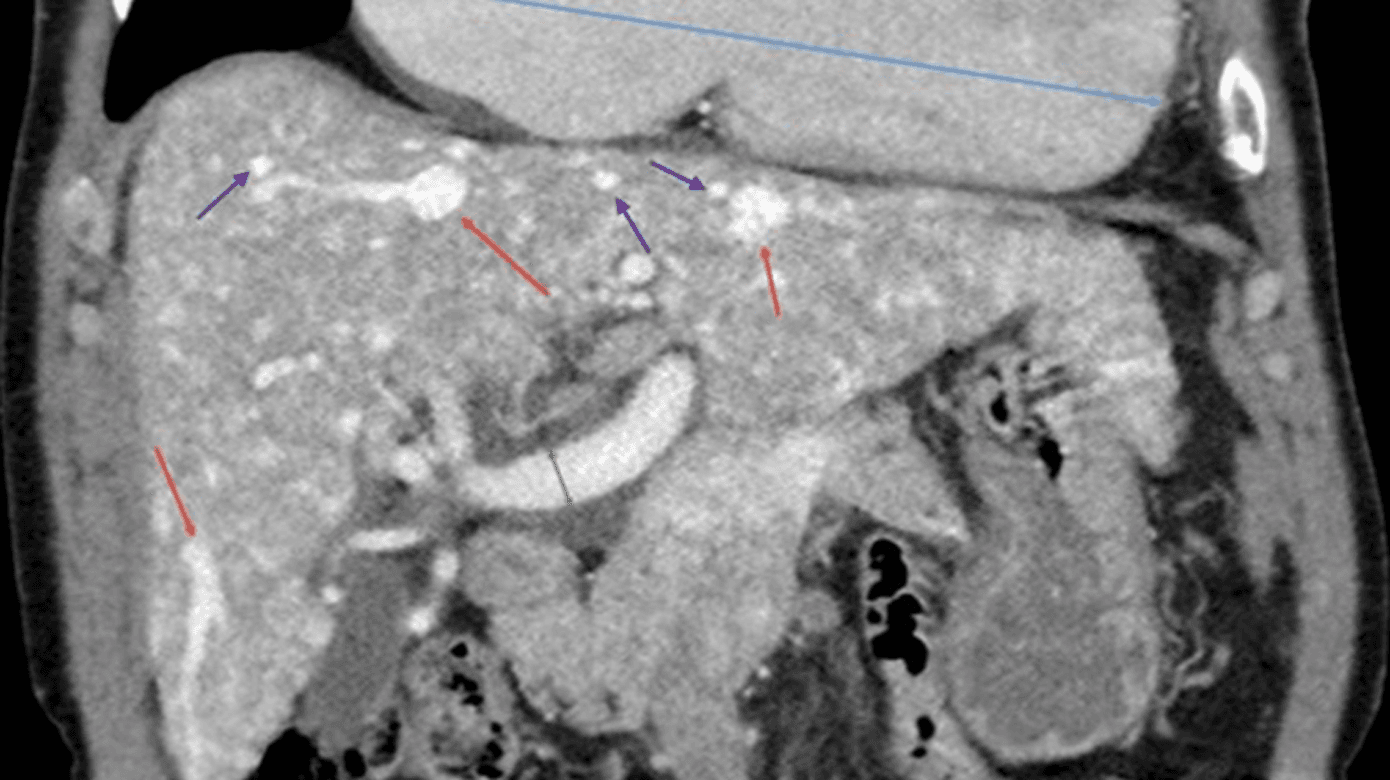

I 2020 udarbejdede Faughnan et al en international guideline, som beskriver diagnosticering, håndtering og behandling af HHT [5]. Den relativt sjældne forekomst af HHT vanskeliggør dog en standardisering, og screeningsprogrammer såvel som behandling beror som oftest på den enkeltes klinikers erfaringer. Det anbefales at screene for HAVM i patienter med HHT, om end der ikke er klare retningslinjer for hyppigheden af screeningen. Flere studier viser, at UL-skanning med Dopplerskanning er ligeværdigt med CT af abdomen med kontrast eller MR-skanning af leveren [8, 16]. I Danmark screenes patienter med HHT med trefaset CT (Figur 2) af leveren aktuelt som 40-årige, og senere i tilfælde af symptomer. Patienter med påviste HAVM, hvor der er symptomer på kardial belastning, tilbydes ekkokardiografi og evt. højresidig hjertekateterisation. Ved fund af fokale forandringer som NRH, FNH og HCC må man benytte sig af MR-skanning til differentialdiagnostik. Der er øget blødningsrisiko ved bioptering, hvilket derfor er relativt kontraindiceret [5, 8, 15].